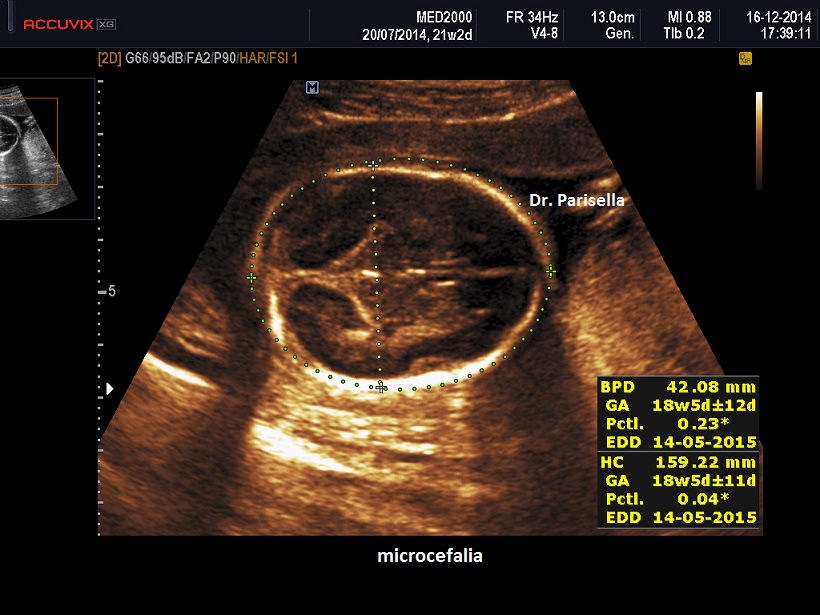

E' la forma più comune di nanismo osteodisplasico microcefalico ed è caratterizzata da nanismo micromelico, microcefalia e ritardo mentale, malformazioni muscolo scheletriche e viscerali. E' anche detta nanismo a testa di uccello  perchè la microcefalia di questi pazienti, con fronte e mento sfuggenti e naso prominente, fa somigliare il loro capo a quello di un uccello. Altre anomalie frequenti del viso sono: occhi particolarmente grandi e distanti, faccia ampia, orecchie ad impianto basso o malformate, micrognatia. Talora sono stati descritti anche clinodattilia, displasia dei fianchi, dislocazione della testa del radio, e altre anomalie più rare.